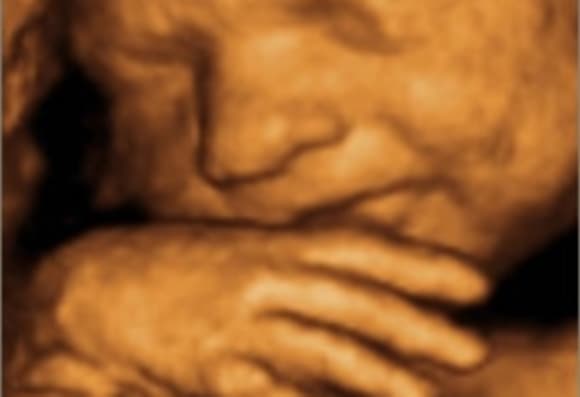

Klinikken kan lave 2D- og 3D-scanninger af barnet gennem hele graviditeten, så længe der er fostervand foran barnet. Det anbefales at komme i uge 24 til 33 som de bedste uger for en 3D/4D scanning med uge 27-29 som de mest optimale. Læs mere under 3D scanning på deres hjemmeside.

Man får en fantastisk cd-rom med levende billeder af scanningen og en strimmel med flotte billeder af barnet (alt efter hvilken uge du bliver skannet i – personalet er søde til at vejlede om hvornår du skal scannes alt efter hvad der kigges efter).